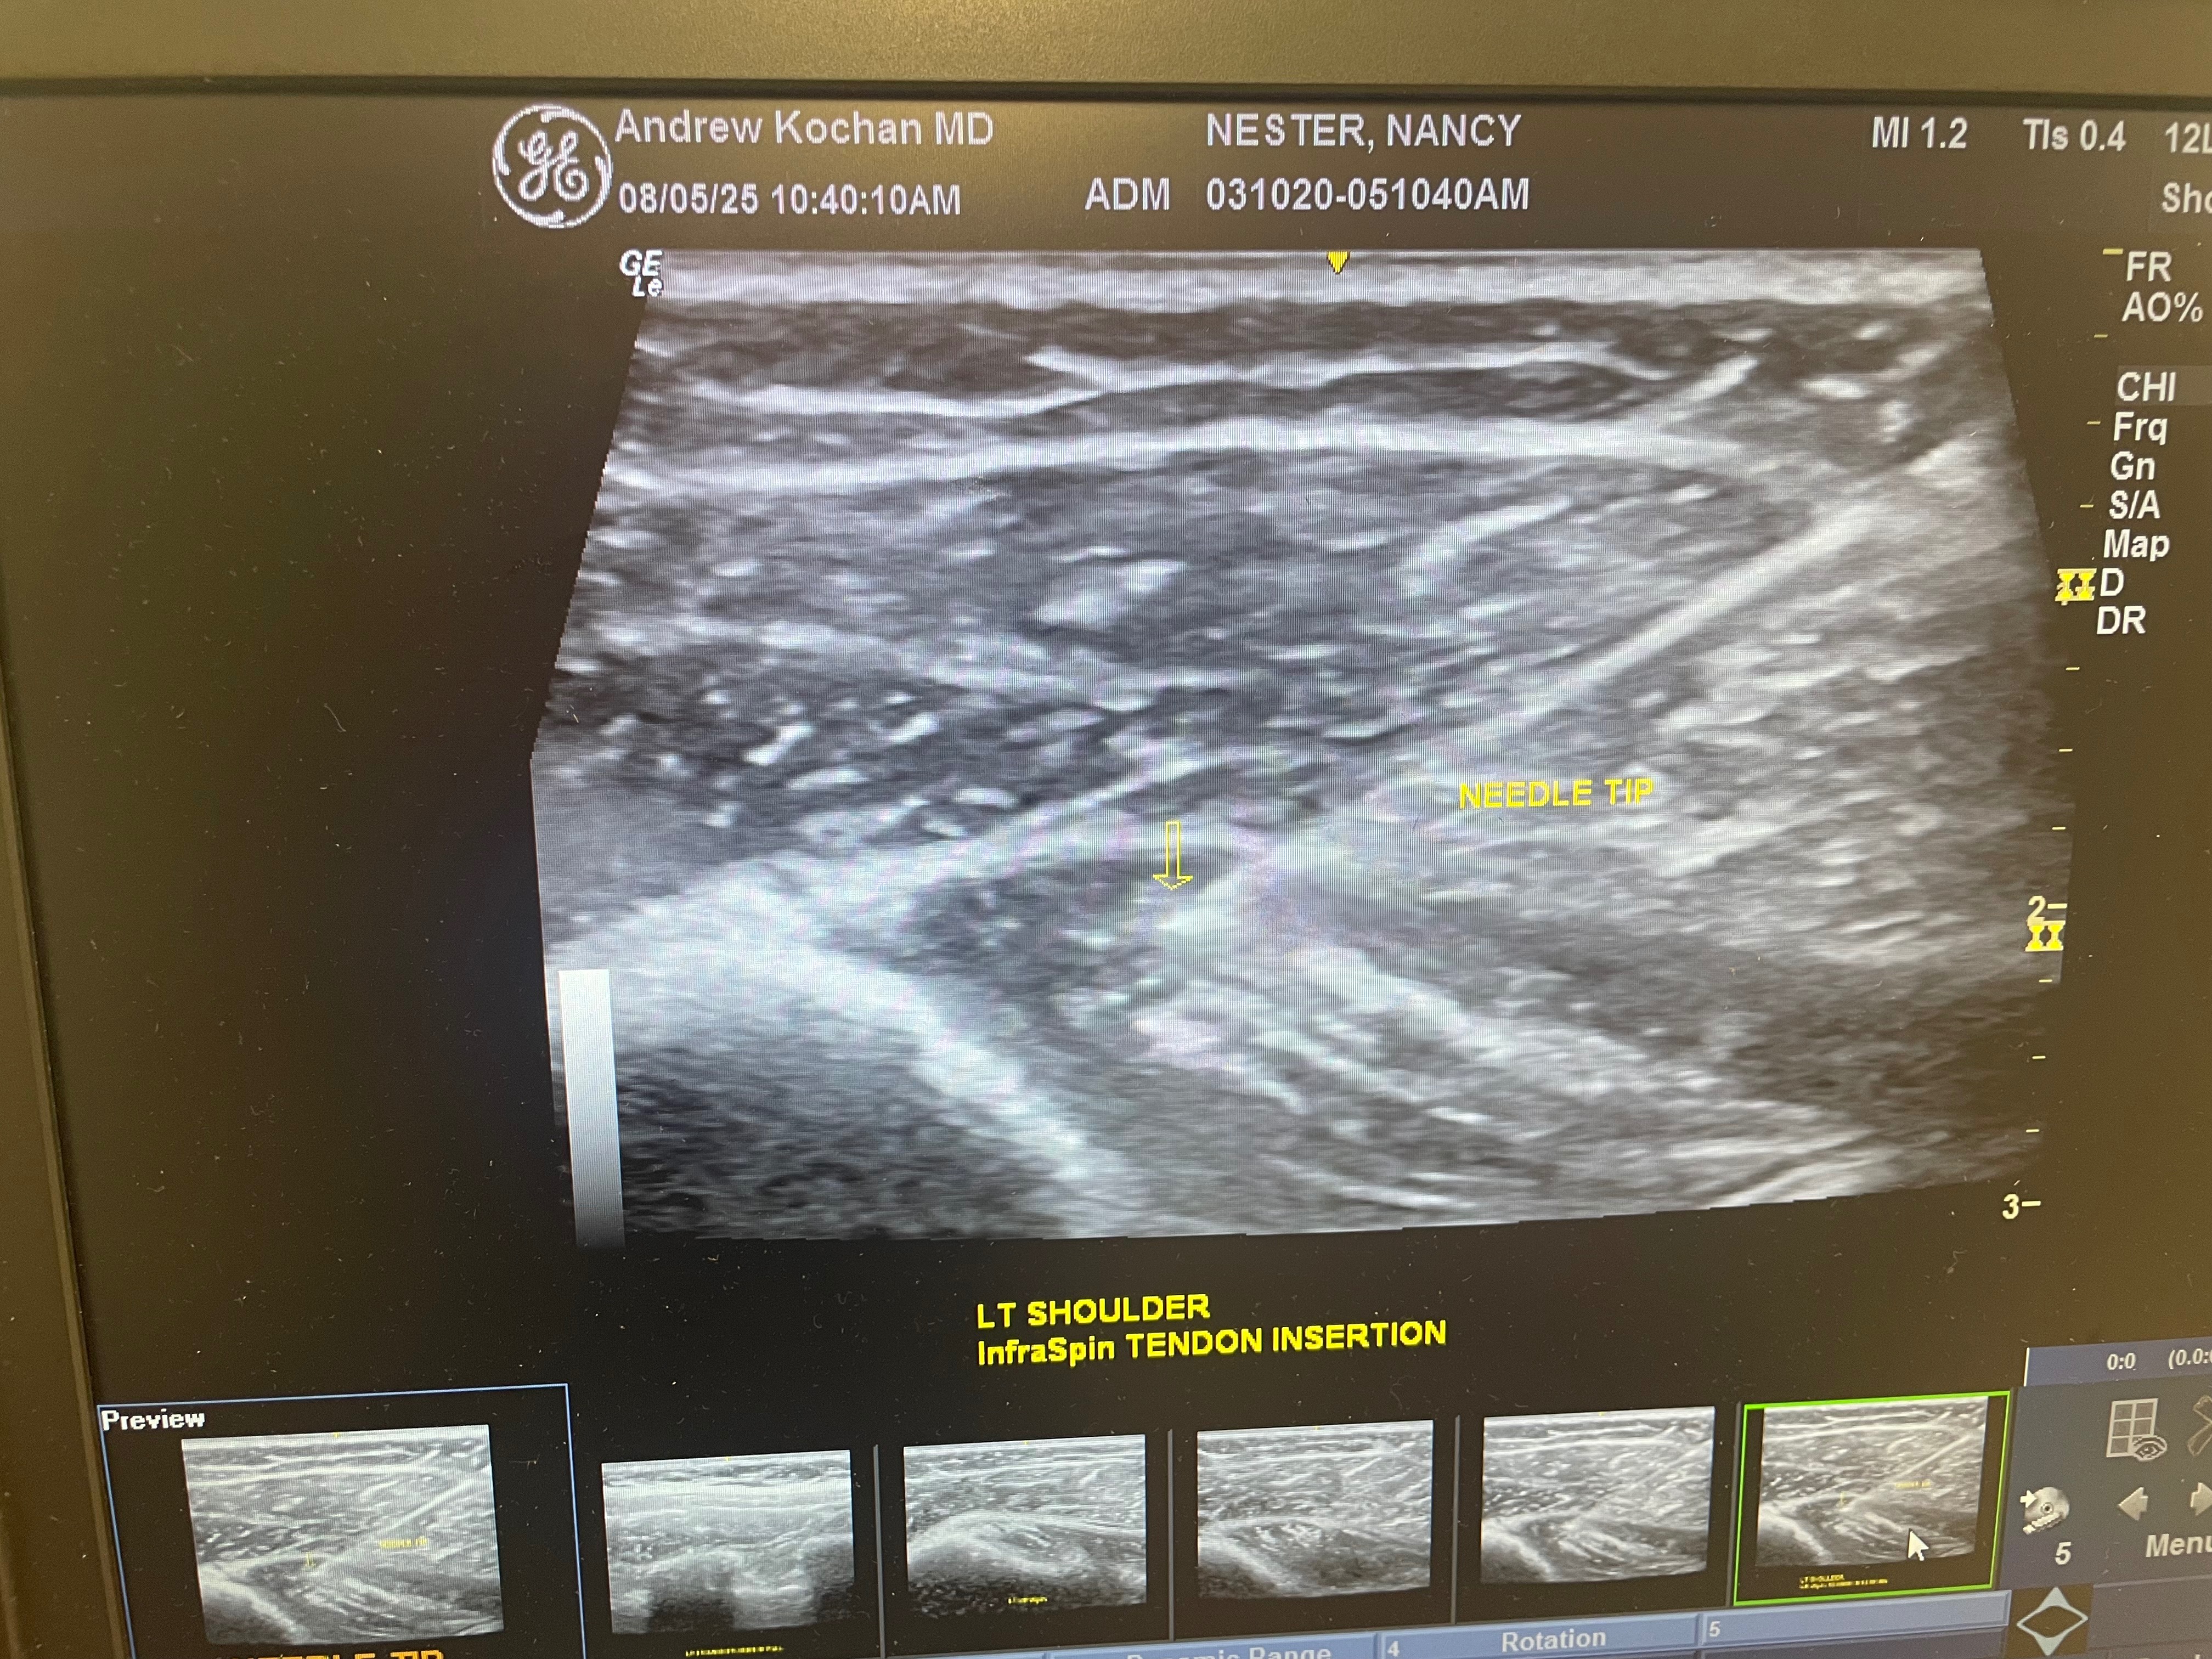

On the 4th of July she was lifted off the ground by her rib cage and tilted and continuously squeezed. Her two ribs 5&6 were popped out and now she is in constant agonizing pain!

These treatments consist of chiropractic rib adjustments and Prolo Therapy injections that only an MD can perform. The treatment will last anywhere from 16-24 weeks weeks!